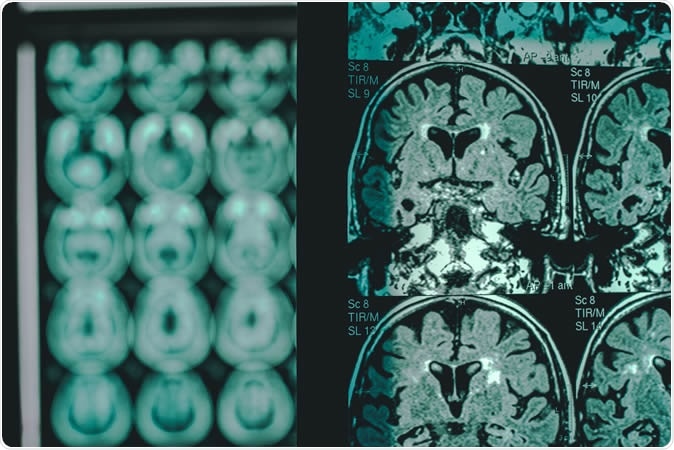

Alzheimer's disease on MRI. Image Credit: Atthapon Raksthaput / Shutterstock